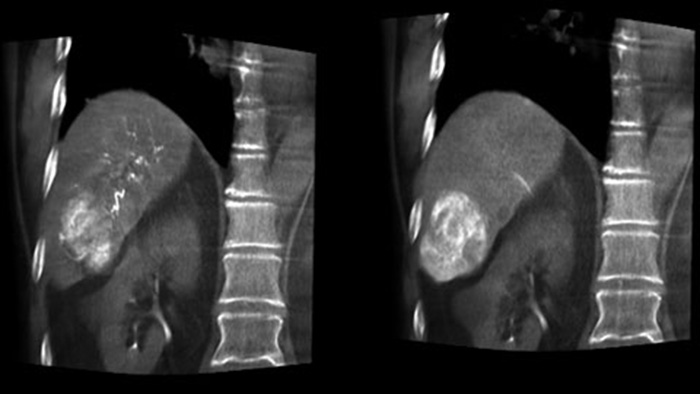

Освобождая пространство слева от пациента, CBCT Open позволяет выполнять позиционирование стола пациента со смещениемот центра и, соответственно, способствует выравниванию поля обзора3-4. Благодаря этому увеличивается охват визуализации, что помогает исследовать опухоли периферических участков печени4.

Функция Dual View позволяет одновременно просматривать два набора данных КТ-подобных изображений. Артериальная и отсроченная фазы могут отображаться рядом друг с другом или в виде объединенного наложения.